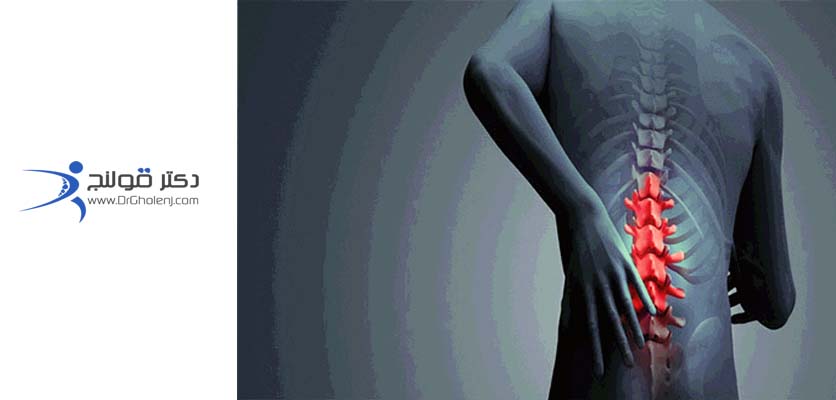

فتق

فتق فیزیوتراپی دراصفهان، به آسیبی گفته میشود که به علت برخورد یا بلند کردن اجسام سنگین یا گاهی به صورت خود به خود در ستون فقرات رخ میدهد و فتق دیسک منجرمیشود در فیزیوتراپی دراصفهان که بخش مرکزی دیسک آزاد شده و باعث فشار بر رویریشههای عصبی بخش محیطی آن و ایجاد علائم بالینی میگردد. دکتر قولنج | drgholenj

فشار به ریشه عصبی | فیزیوتراپی دراصفهان

فتق دیسک به علت ساییدگی تدریجی و پارگی خود به خود بخصوص در افرادی که کار نشسته دائمی دارند اتفاق می افتد، اما در افرادی که به حمل و نقل اجسام سنگین اشتغال دارند بیشتر از افراد دیگر است. در اثر این پارگیها، بیماران دورههای طولانی و خفیف درد را دارند، ولی در پارگیهای حاد، درد به صورت ناگهانی و شدید است. فشار داخل دیسک در حالت ایستاده کمتر از حالت نشسته و در حال نشسته کمتر از موقعی است که شخص در حالت ایستاده بطرف پائین خم میشود. در حالت خم شدن زیاد، هسته مرکزی دیسک به لبه پشتی الیاف کروی دور خود فشار آورده و آن را در صورت ضعیف شدن پاره میکند و به ریشه عصبی دیسک فشار وارد میکند.

هرچند دیسکی که بر اثر فشار، بیرون زده، از عوامل اصلی علائم بالینی است، اما رادیکولیت شیمیائی امروزه یکی از عوامل مهم در ایجاد درد کمر محسوب میشود و نمیتوان فقط وجود فشار روی نخاع یا ریشه عصبی را تنها عامل ایجاد درد دانست. آزاد شدن این فاکتور التهابی که به طورعمده از پارگی دیسک بوجود می آید، باعث تخریب و انحطاط بقیه دیسک شده و این التهاب در ایجاد درد موثر است. همچنین بعضی گزارشهای علمی در این راستا به عمل آمده نشان میدهد گه عوامل ژنتیکی و جهش ژنی در ایجاد فتق دیسک بسیار موثر میباشد. drgholenj